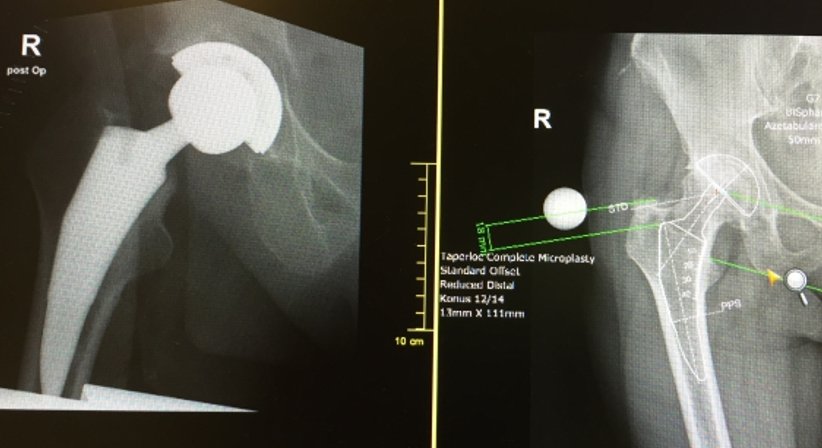

Operation/Hüftprothese

Bei Patienten mit ausgeprägter Hüftarthrose, bei welchen konservative Therapien nicht mehr wirksam sind, sollte die Implantation einer Hüftprothese (künstliche Hüfte) in Betracht gezogen werden. Hüftarthrose im fortgeschrittenen Stadium wirkt sich auf das allgemeine Wohlbefinden aus und kann zu starken Einschränkungen der Mobilität und Selbstständigkeit führen. Durch eine Hüftprothese werden die Schmerzen und die Beweglichkeit nachhaltig gebessert, was folglich auch positive Auswirkungen auf die Vitalität und andere Lebensbereiche hat.

Hüftprothesen ahmen die Form und die Funktion eines normalen Hüftgelenks nach. Für den Hüftgelenksersatz stehen unterschiedliche Prothesen (z. B. Prothese mit Keramikl-Polyethylen-Gleitpaarung, Prothese mit einer Gleitpaarung aus Keramik-Kerami etc.) und Operationsverfahren zur Verfügung. Ich führe die Operation bei Möglichkeit nach der AMIS-Methode durch. Hierbei handelt es sich um einen minimal-invasiven Eingriff, bei welchem der operative Zugang von vorne und nicht von der Seite erfolgt. Hierdurch ergeben sich zahlreiche Vorteile wie etwa: